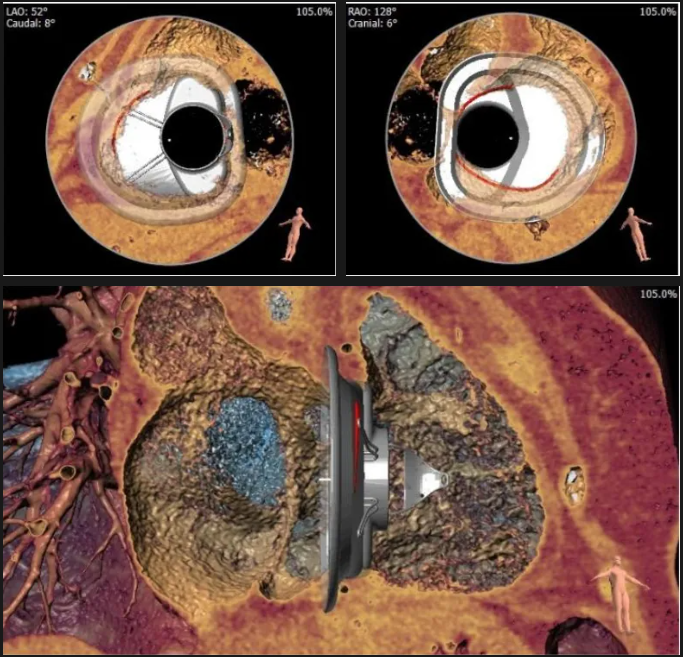

術(shù)前心臟CT評(píng)估

三尖瓣環(huán)平均周長(zhǎng)徑54.3mm,最大直徑57mm

心房側(cè)周長(zhǎng)平均徑(封堵高度)74.0mm

三尖瓣環(huán)切線位夾角 103°